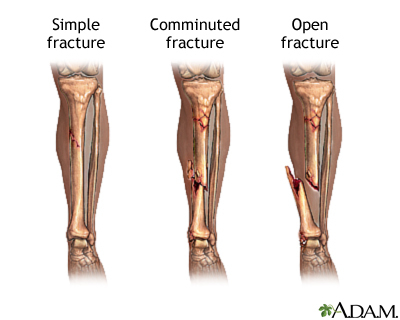

What does comminuted fracture mean?

More than two fracture lines - results in multiple bone fragments